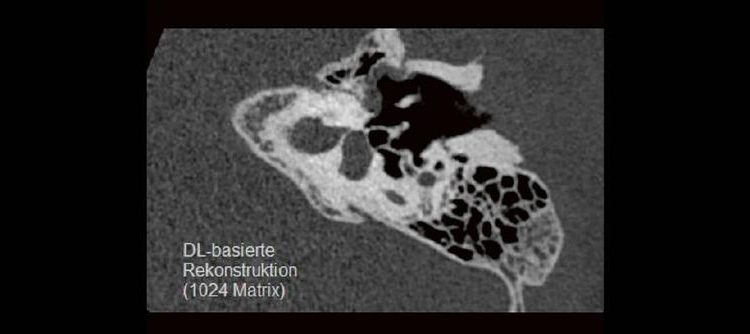

Professor Dr. med. Marc Brockmann WEITERENTWICKLUNGEN VON KOPF BIS FUSS BEIM VC Oberstarzt Dr. med. Stephan Waldeck DEEP-LEARNING-REKONSTRUKTION IN DER NEURORADIOLOGIE Die CT ist ein essentielles Routine-Verfahren in der Neuroradiologie. Bei steigender Bildqualität konnte die Röntgendosis mit neuen Technologien in der letzten Dekade deutlich gesenkt werden, was für die zielgerichtete und möglichst schonende Behandlung von […]